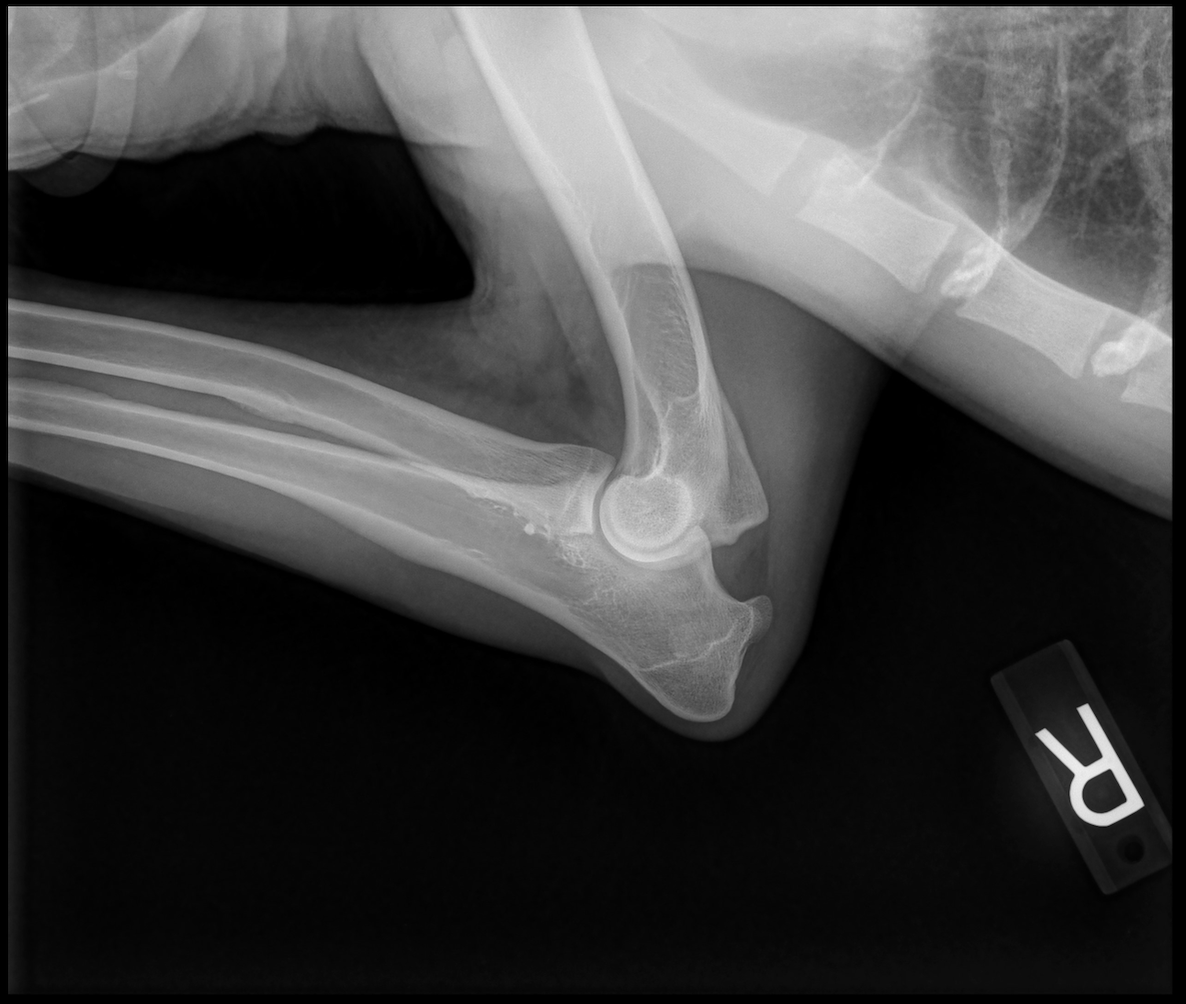

---- OFA Hip & Elbow Imaging ----